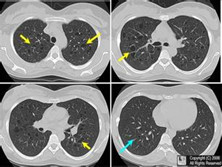

肺组织细胞增生症(肺组织细胞增多病、肺组织细胞增多症)

肺组织细胞增生症即肺朗格汉斯组织细胞增生症(PLCH),以前被称为肺嗜酸性粒细胞肉芽肿,肺组织细胞增多症X,是一种发病率较低的疾病。肺可单独受累或成为全身多器官受累的一部分,患者多为成年吸烟男性。

• 应该做哪些检查项目呢?血常规、胸部CT、红细胞沉降率检测、X线平片、肺功能检查、支气管镜